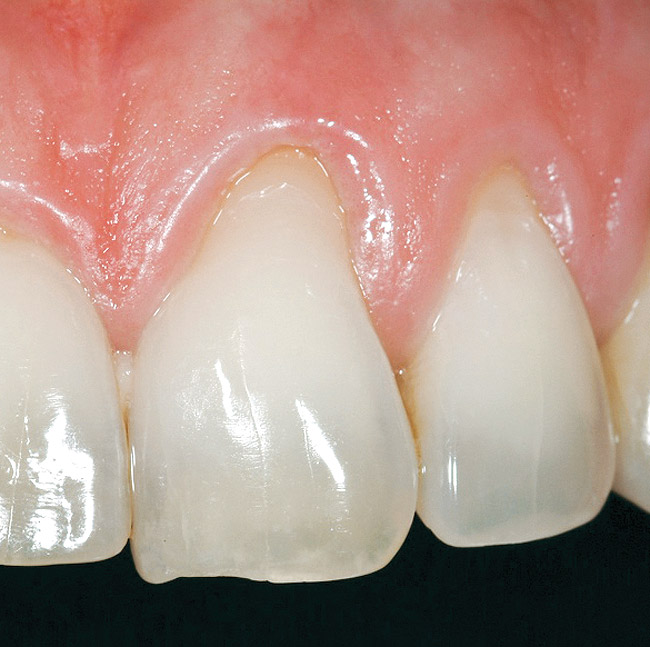

A 54-year-old non-smoking woman presented for correction of deep-wide gingival recession in the maxillary anterior (Figure 1 through Figure 3). The patient’s desires were to correct the gingival recession, balance the heights of contour of the tissues, and possibly undergo esthetic enhancement of the maxillary anterior with veneer restorations.

Figure 1  Case One Pretreatment clinical view, Case 1, maxillary right.

Figure 1

Figure 2  Case One Pretreatment clinical view, Case 1, maxillary anterior.

Figure 2